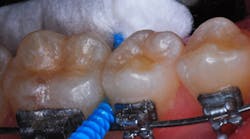

- After lightly air-drying but not desiccating the tooth, Lime-Lite Enhanced base/liner was injected with care to avoid air inclusion (figure 3a) and light-cured (figure 3b).

- The preparation was completed using a slow-speed inverted cone bur (figure 3c).

- The preparation and surrounding enamel were painted with a self-etching bonding agent (Adper Prompt L-Pop Self-Etch Adhesive).

- After 30 seconds, ACTIVA BioActive Restorative was injected to overfill, and a ball burnisher was used to spread the material so it overlapped the cavosurface margins (figures 4a and 4b).

- A curing light beam with an output of 1,100 mW/cm2 polymerized the material.

- Using a large, round diamond bur at slow speed, the hardened material was trimmed to contour (figure 4c), and a final “glaze” of bonding agent was painted and light-cured on the surface (figures 5a and 5b).